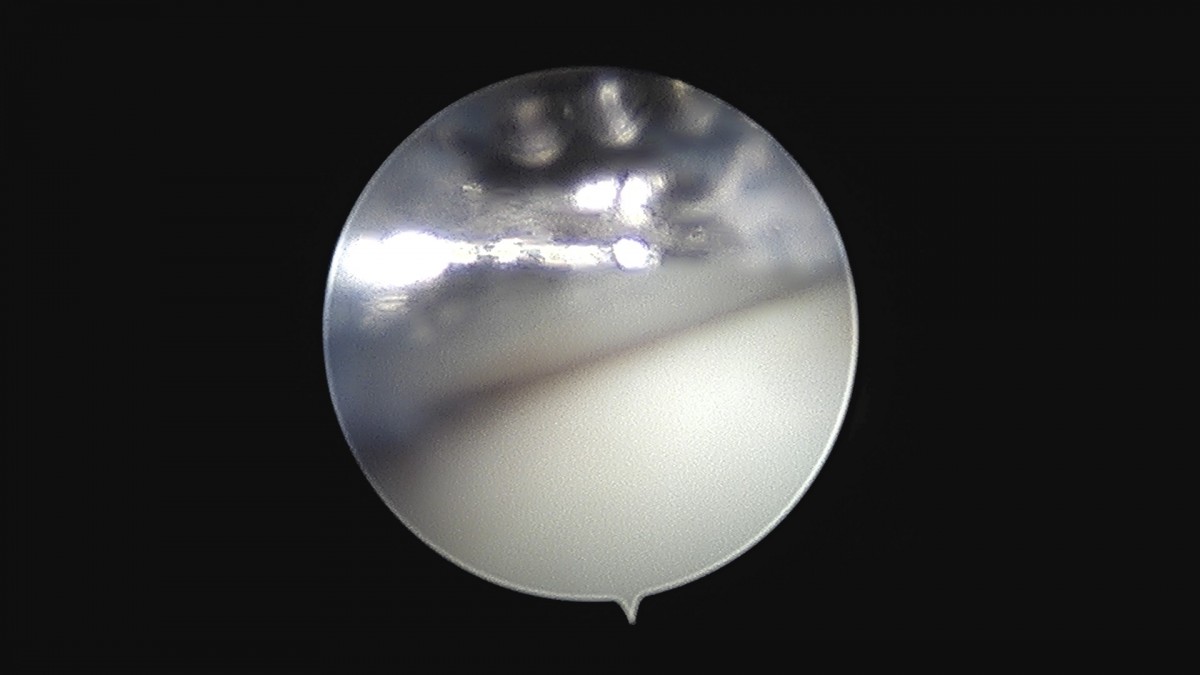

이재상원장님 무릎 변연절제술 권오O 환자

작성자 최고관리자 댓글 0건 조회 373회 작성일 25-09-16 16:11